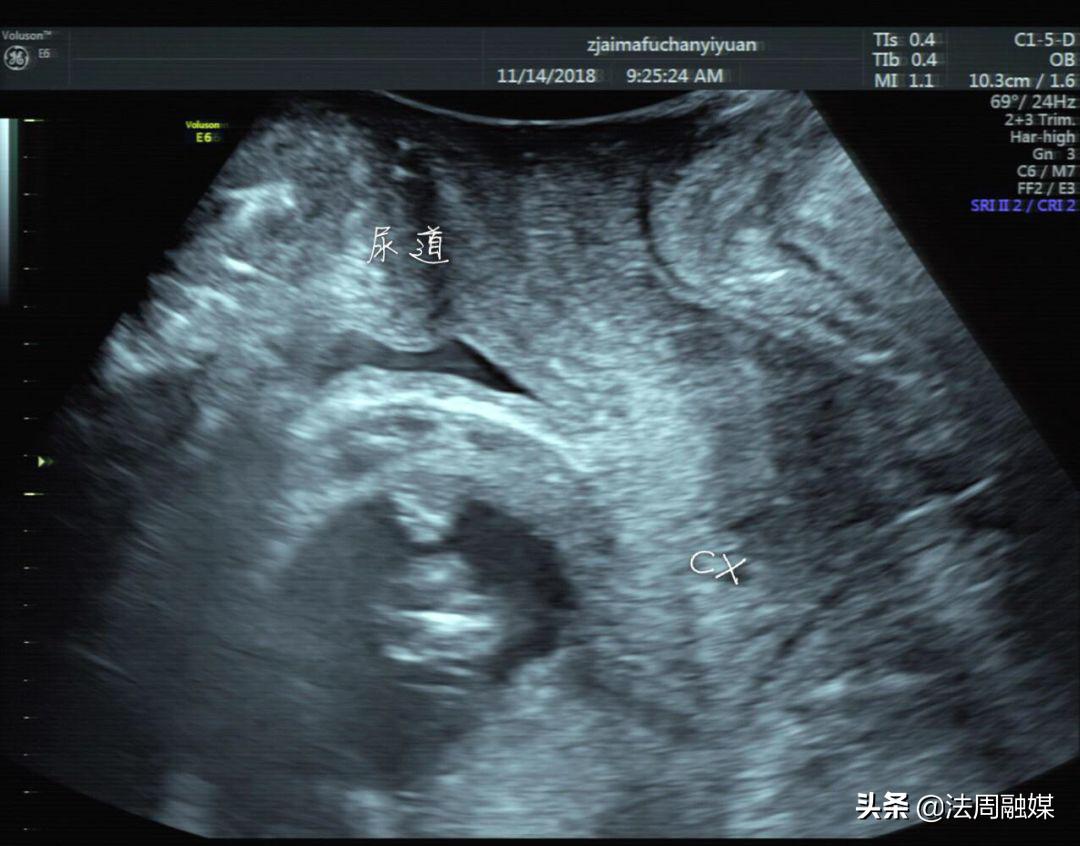

尿潴留缓解,子宫位置已转前位,宫颈远离尿道

尽管病因非常少见且病情凶险,但专家们还是凭借丰富的从医经验,迅速且精准地为患者找到了病根,并第一时间制定了治疗方案。当天上午,首诊杨御华主任为何女士插上导尿管,引流出500ml尿液后,何女士明显感觉疼痛缓解。随后,何女士被送往产科门诊观察及护理,夹闭后15分钟再次放出500ml尿液。观察半小时后,生命体征平稳,于下午再次引流出尿液1000ml,杨御华为其行手复位后在病房留观。4月6日,何女士顺利出院,杨御华嘱其行膝胸卧位一周,观察排尿情况,如有不适随诊。4月7日,经电话回访,目前何女士排尿正常,没有任何不适,母子平安。